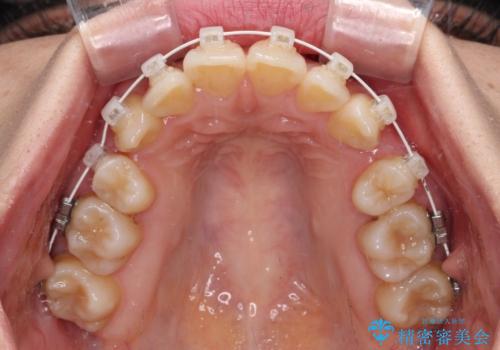

デコボコで磨きにくい歯列 ワイヤー装置での抜歯矯正で歯磨きをしやすく

- デコボコの歯列で歯磨きがしにくいことを気にして来院された患者様です。

右側の上下は歯が重なり合って、内側に移動してしまうほどであり、それに伴って正中の位置が右側にずれている状態でした。

上下左右の第一小臼歯4本を抜歯して行うことになりますが、それだけでは咬み合わせの改善や正中位置の改善が困難であると判断されたため、アンカースクリューを用いた補助装置を併用することで、スムーズかつより良い仕上がりを目指すこととしました。